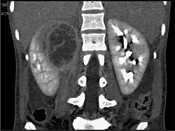

- 单项选择题一女性患者,一月前出现尿频、尿急等症状为引起注意, 现有高热,阅图后最可能的诊断为 ( )

A、急性肾盂肾炎

B、肾脓肿

C、多囊肾

D、肾结核

E、肾癌